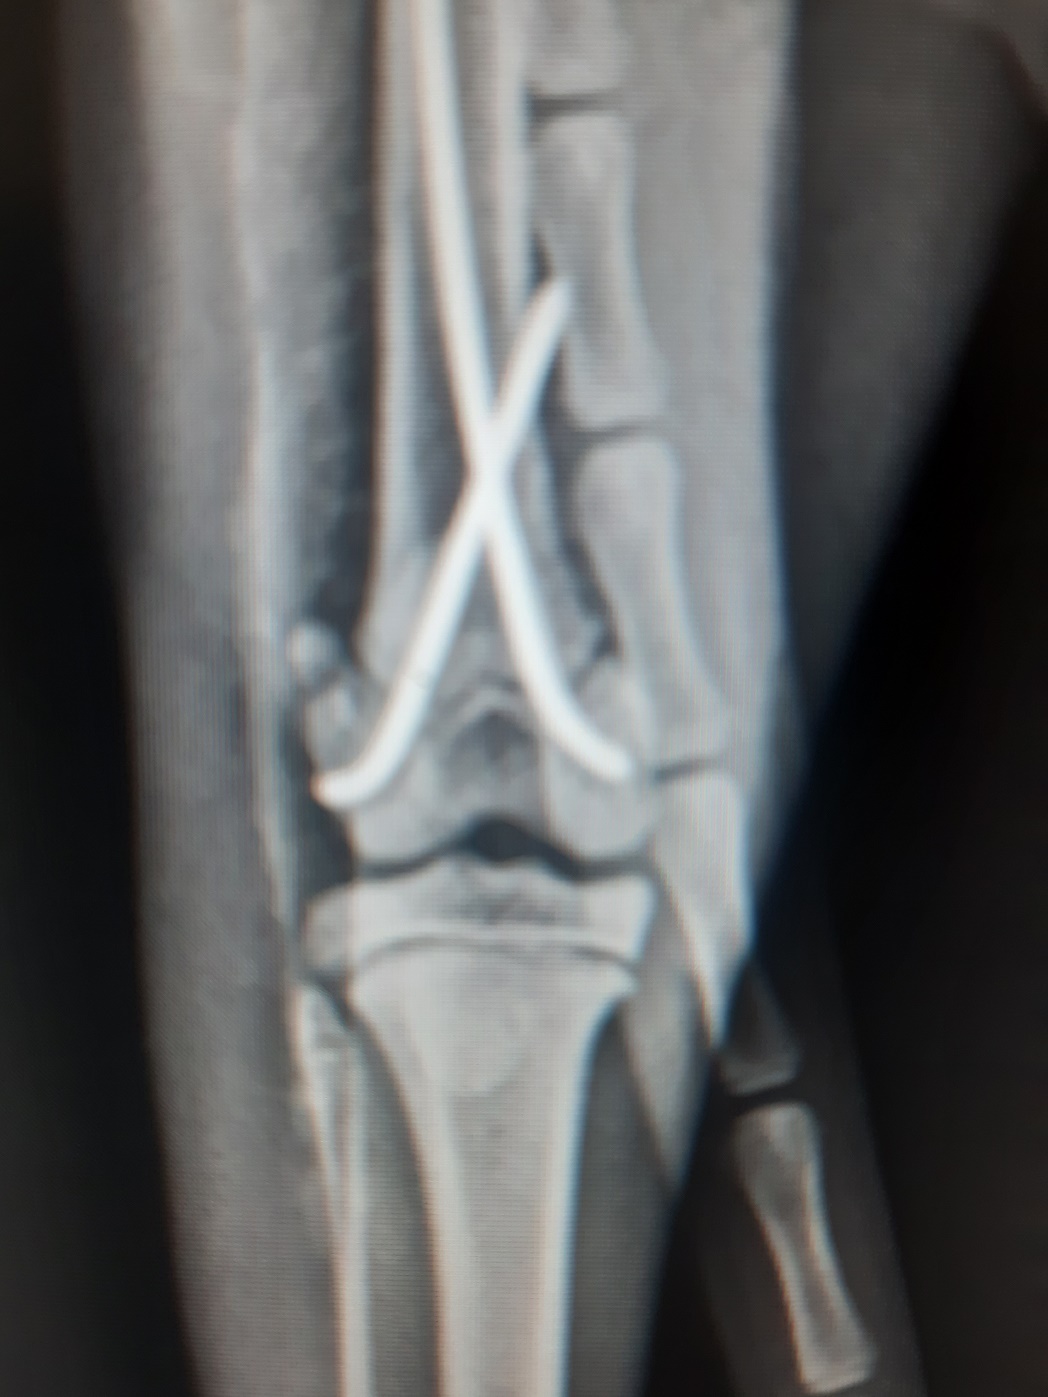

Ein kleiner Rückblick noch auf den Dezember, der uns viele interessante Patienten gebracht hat!